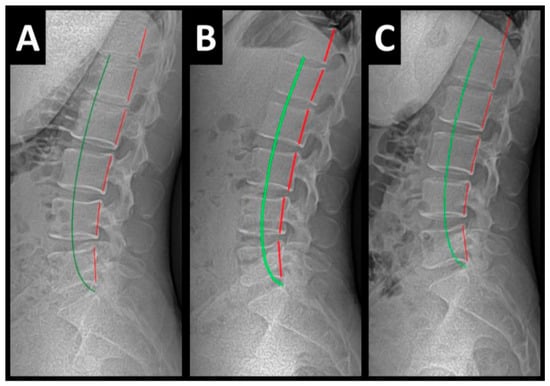

Radiography of the spine was performed with the patient upright in neutral position. Anterior–posterior (AP) and lateral films were assessed using PostureRay® digital radiographic mensuration software (Posture Co, Inc., Trinity, FL, USA) [14]. The program uses the Risser–Ferguson measurement for the AP views and the Harrison posterior tangent method (HPTM) of measurement for the lateral views. The program also compares the patient alignment of both segmental and global measurements to models of ideal spine parameters; prior studies have shown exceptionally high reliability using this system [15]. The sagittal spine absolute rotation angle (ARA) from the 2nd cervical vertebra to the 7th (ARAC2–C7) measured −18.1° (average is −34°, ideal is −42°, pain threshold is −20° [16]) (Figure 2, Figure 3, Figure 4 and Figure 5) and the AP cervical X-ray demonstrated a right lateral flexion angle relative to true vertical of the lower cervical and upper thoracic spine (cervicodorsal angle (CDA)) measuring 5.6° (ideal is 0° [16]) with a right translation of C2 with respect to T5 (TXC2–T5) measuring −17.2 mm (ideal is 0 mm). There was an increased mid-thoracic angle with a right-sided concavity from T1 to T12 (MTAT1–T12) of 9.1° (ideal is 0° [16]) with an increased translation at T8 apex of mid-thoracic angle with respect to T12 (+TXT8–T12) measuring 15.2 mm (ideal is 0 mm). There was a decreased sagittal curvature of the lumbar spine from L1 to L5 (ARAL1–L5) measuring −17.9° (ideal is −40°, average range is 35–45° [16]). The modified Ferguson pelvic radiograph demonstrated a sacral base unleveling in the frontal plane measuring −11.3 mm, being lower on the right. There was a lumbosacral angle from L1 to L5 with an L3 apex (LSA L1–L5) of −84.9° (ideal is 90°).

Post-treatment posture analysis showed improved posture (Figure 1A–C). Post-treatment radiographic examination revealed the following: improved ARAC2–C7 measuring −29.4° (vs. −18.1°); rotation around the z-axis of the thorax (RZT5) measured 1.8° (vs. normal 0°); improved -TxC2–T5 measuring −5.7 mm (vs. −17.2 mm); improved MTA T1–T12 measuring 2.1° (vs. 9.1°); improved +TxT8–T12 measuring 3.5 mm (vs. 15.2 mm); improved ARAL1–L5 measuring −25.1° (vs. −17.9°); improved sacral base unleveling in the frontal plane measuring −1.0 mm low on the left (vs. −11.3 mm low on the right); and improved LSA L1–L5 of −88.0° (vs. −84.9°) (Figure 2B, Figure 3B, Figure 4B and Figure 5B). Post-treatment RODI score was 12% (vs. 54%), indicating minimal disability. All post-treatment SF-36 scores showed improvements (Table 1). One-year follow-up posture analysis showed a maintenance of the improved posture. One-year follow-up radiographic examination revealed maintained sagittal balance and coronal spinal alignment correction improvements (Figure 2C, Figure 3C, Figure 4C and Figure 5C). One-year follow-up RODI score was 2% indicating minimal or resolved disability from baseline (54%). Post-treatment SF-36 scores showed maintained or further improved HRQoL measures reported by the patient. Long term follow-up found minimal forward head posture on the lateral posture photograph, a slight return to baseline on the A-P cervical radiograph with a right head translation measuring 7 mm. Lateral cervical radiograph assessment at long-term found the lordosis to be well maintained at 34° ARA with minimal C2-vertical anterior head translation of 6 mm. lateral lumbar radiograph showed a slight loss of lordosis at follow-up of 19°. All subjective initial symptoms were reported to be resolved at long-term follow-up. Long term follow-up SF-36 scores were the same as post-treatment with the exception of vitality, which was slightly improved (Table 1). There were no positive orthopedic or neurological tests at follow-up. The patient continued to use the ProLordotic neck exerciser at home 1–3 times per week for up to 10 min (Figure 7).

Figure 5. (AC) Pre-treatment, post-treatment, and 1-year follow-up lateral lumbar radiographs. Image Features: The green line represents a normal, ideal sagittal lumbar spinal alignment. The red line represents the actual lumbar alignment of the T12–L5 vertebrae.